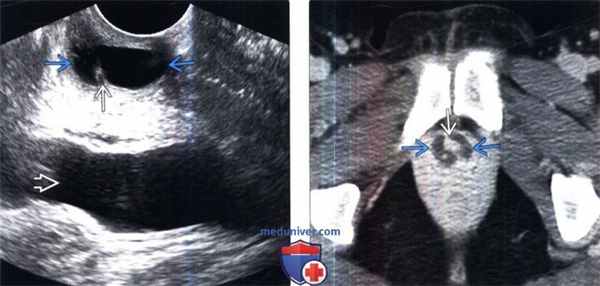

(Слева) Трансвагинальное УЗИ под углом в корональной плоскости: овоидная кистозная структура, окружающая уретру. Кистозная структура анэхогенная и обладает задним акустическим усилением. Более кверху и кзади определяется мочевой пузырь.

(Справа) КТ с контрастированием на уровне лобкового симфиза, аксиальный срез: у этого же пациента определяется округлая кистозная структура, окружающая уретру, вследствие наличия дивертикула. Контрастирование уретры и соседних тканей нормальное. Ранее отмечалось подтекание мочи после мочеиспускания.